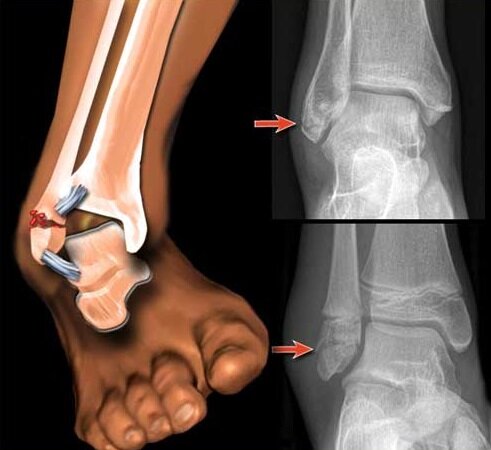

Перелом Латеральной лодыжки.

Я закрыл двери ключами и лёг! и написал маме как будешь заходить домой открой домофон сама и дверь открой ключами. Лёг на кровать , до этого момента и ещё мог наступать на ногу ! мама зашла домой и спросила что с тобой? Я ей всё объяснил что со мной произошло! она меня спросила а почему ты не вызвал скорую? я ответил, я побоялся тебя беспокоить! после этого мы поехали в трампункт и нам сказали у нас не работает ренген!! Мы вам сейчас вызовем скорую и вы поедете ! после этого приехала скорая и нас забрали. И отвезли в больницу когда мы приехали в эту больницу , меня смотрели сделали ренген , хотя мы боялись того что нельзя делать часто ренген !так как я сегодня уже делала ренген лёгких ! но не суть врач осмотрел ногу и посмотрел снимки и сказал что у меня перелом латеральный ладышки.

Вы можете представить какой был у меня шок! когда я думал что у меня просто разрыв связок! Я со сломанной ногой ехал с гражданского проспекта до московской!! через весь город домой! я повторюсь со сломанной ногой!! через весь город! и ещё успел зайти в поликлинику сделать ренген лёгких со сломанной ногой! мне наложили гипс и сказали быть дома четыре недели!

Очень хорошо что мне повезло! что у меня обычный перелом без смещения без осколков костей!